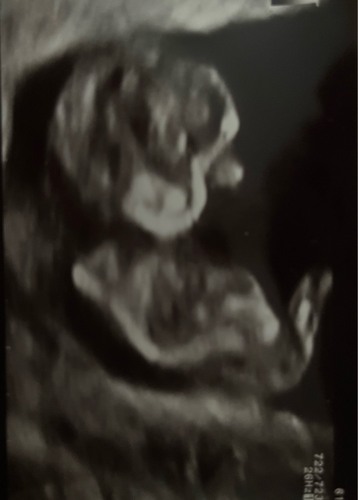

Dit was met 13 weken. Wie durft een gokje te wagen?

jomgen